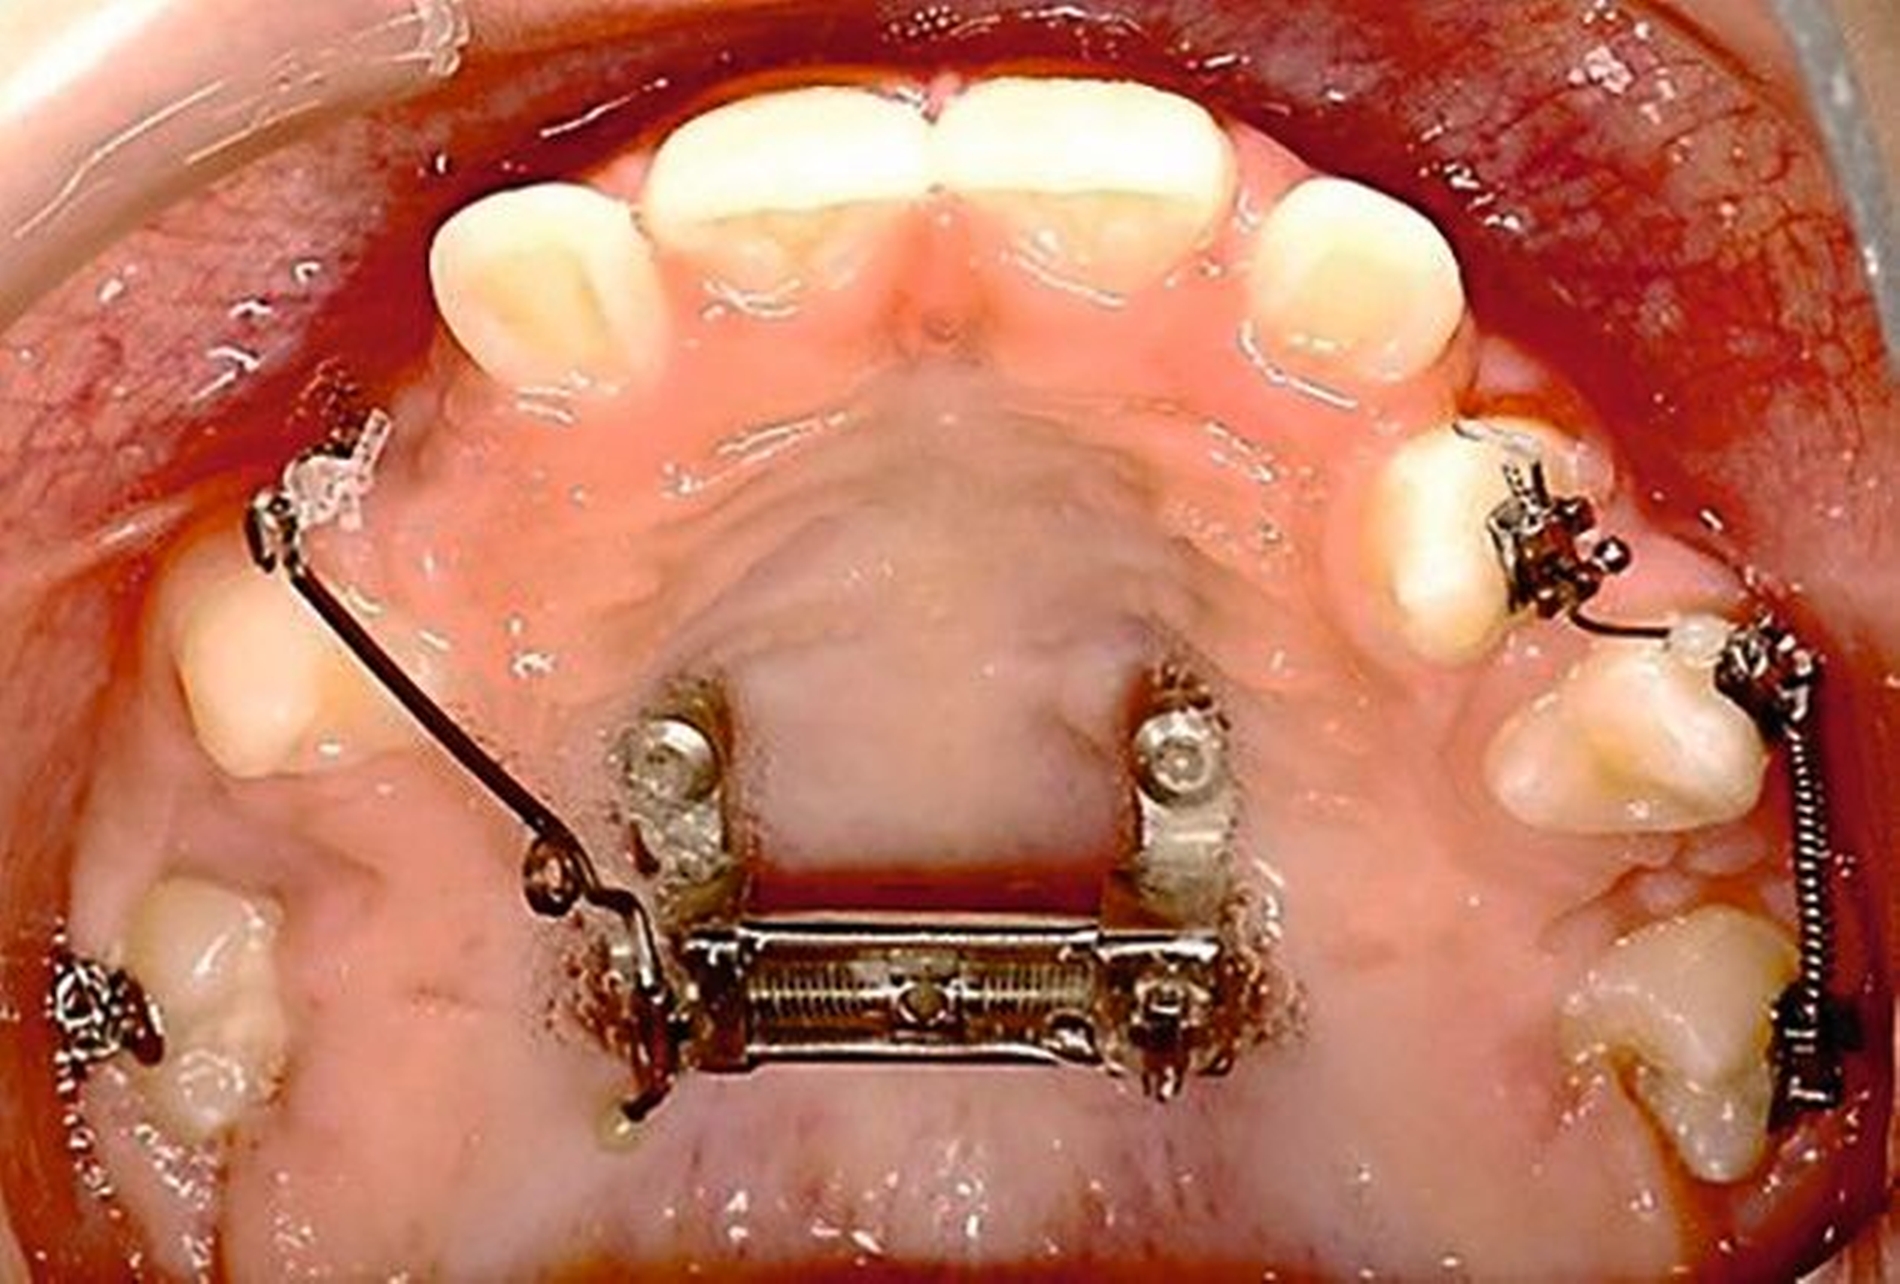

Ein zwölfjähriger Patient stellte sich in der Poliklinik für Kieferorthopädie des Universitätsklinikums Tübingen mit einer skelettalen Klasse-III-Konfiguration, einer Angle-Klasse III, einem Kreuzbiss auf der linken Seite und transversal schmalem Oberkiefer vor. Die Anamnese ergab ein vermindertes Hörvermögen, weshalb der Patient Hörgeräte trug. Darüber hinaus wurde keine Medikamenteneinnahme oder Allergie angegeben. Er wies mit einem dentalen Alter von sieben Jahren einen verzögerten Zahndurchbruch auf. Der initiale intraorale Befund zeigte die in situ befindlichen Zähne 11, 21 und 32–42. Die Zähne 12 und 22 eruptierten in Inklinationsfehlstellung. Die Milcheckzähne und -molaren befanden sich noch in situ. Die Sechsjahrmolaren waren nicht eruptiert und zeigten eine Verlagerungstendenz, insbesondere im Unterkiefer (Abbildung 1, Tabelle 1).

Die initiale Panoramaschichtaufnahme zeigte die Verlagerung mehrerer Zahnkeime sowie einen Platzmangel der Eckzähne und der Prämolaren im Oberkiefer (Abbildung 1b). Die Keimkrone von Zahn 13 wies dabei eine enge Lagebeziehung zum Zahnkeim 12 auf (Abbildung 1b). Die bereits eruptierten permanenten Frontzähne zeigten eine Angulations- und eine Inklinationsfehlstellung. Im distalen Bereich waren keine Durchbruchshindernisse erkennbar. Vor Beginn der kieferorthopädischen Behandlung wurde eine Primäre Zahndurchbruchsstörung (Primary Failure of Eruption – PFE) genetisch ausgeschlossen.

Die Zähne 36, 37, 46 und 47 wurden in Allgemeinanästhesie chirurgisch freigelegt. Zusätzlich wurden die beiden paramedianen Mini-Implantate (2 x 9 mm, Benefit System; PSM North America, Indio, CA) ohne Vorbohren mithilfe der zuvor hergestellten Schablone inseriert (Abbildung 3). Für die Platzierung der Mini-Implantate wurde ein Winkelschraubendreher verwendet. Direkt nach der Operation wurde die bmx DIRECT Hyrax-Schraube (10 mm, BENEfit®-System, Dentalline, Birkenfeld, Deutschland) an den Mini-Implantaten befestigt, um ein MARPE zu erzielen (Abbildung 4).

Die Eltern des Patienten wurden angewiesen, die Schraube einmal täglich zu aktivieren. Die gesamte Aktivierungszeit der Hyrax-Schraube betrug circa zehn Wochen. Während dieser Zeit vergrößerte sich die transversale Dimension des Oberkiefers um sieben Millimeter im posterioren Bereich (Milchmolaren) und um fünf Millimeter im anterioren Bereich (Milcheckzähne). Währenddessen trat ein mediales Diastema auf (Abbildungen 4b und 4c), das auf eine skelettale transversale Expansion des Oberkieferknochens hinwies. Nach der aktiven Expansionsphase der Hyrax-Apparatur wurde das Gerät für weitere Behandlungszwecke verwendet: Erstens als Retentionsgerät, um die bereits erzielte transversale Oberkieferbreite zu halten und zweitens als skelettal verankerte Apparatur zum Einstellen der retinierten und verlagerten Zähne mithilfe individuell angefertigter Kragarme. Hierfür wurde die Hyrax-Apparatur im zahntechnischen Labor modifiziert, indem Kreuzröhrchen für eine stationäre Befestigungen für die Drähte des Kragarms angebracht wurden.